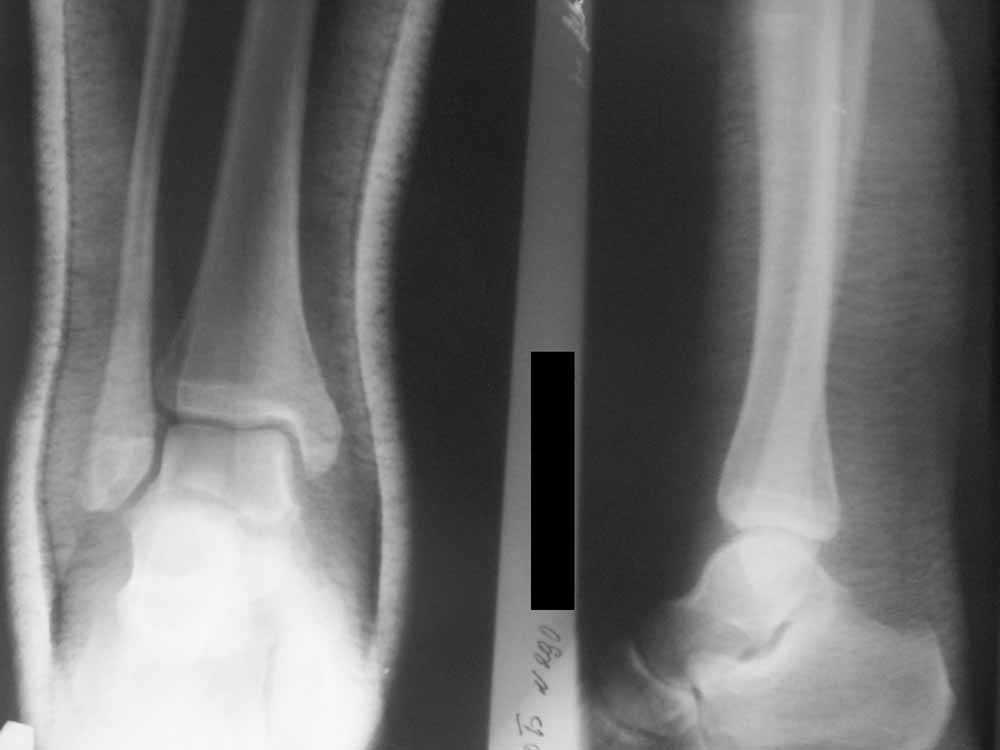

Уважаемые коллеги!Помогите, пожалуйста, советом! Пациентка 14 лет. Двухлодыжечный перелом с (как нам кажется) повреждением межберцового синдесмоза. Вопрос один: оперировать или оставить "как есть" в гипсе? Не будет ли в дальнейшем проблем с суставом. Заранее спасибо.

Уважаемый Сергей! Я не навязываю свое мнение, но по моему, ребенка в данном случае нужно лечить консервативно в гипсовой повязке. Старая мудрость "Хирург славен не теми операциями которые он сделал, а теми от которых он отказался" На мой взгляд по тем снимкам которые представлены, суставная щель по ширине одинакова по всему суставу, значит "вилка" удерживающая таранную кость не разошлась. С уважением Евгений.